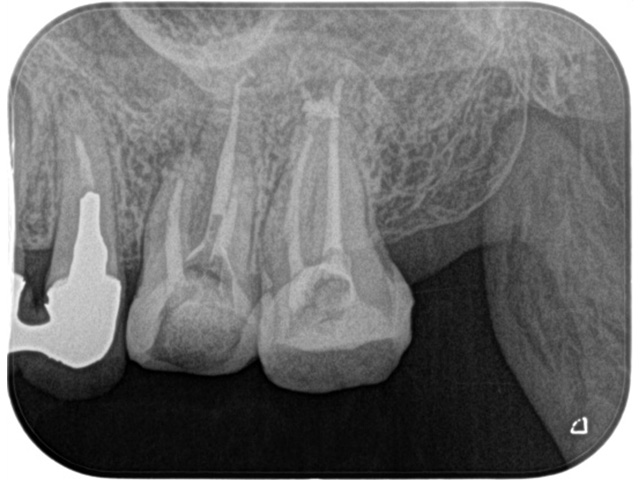

Before

After

| 主訴 | 右上の奥歯が咬むと痛む |

|---|---|

| 治療内容 | 右上第一大臼歯、第二大臼歯の精密根管治療 |

| 治療回数・期間 | 3回(3週間) |

| 費用 | 保険適応 |

| リスク・副作用 | 根管治療は術前の精密な診査診断および無菌環境下での治療によって成功率は高まってきましたが治療の成否を決める多くの要素があるため、根管治療がなされた後も再治療や外科処置、抜歯となる可能性が少なからずあります。また治療中には器具の破折や穿孔、修復物の損傷、歯の破折、術中・術後の痛みや腫れが生じることが稀にあります。根尖病変(再感染)を防ぐには適合の良好な補綴物を作製することや定期的なかみ合わせのチェックが必要です。 |